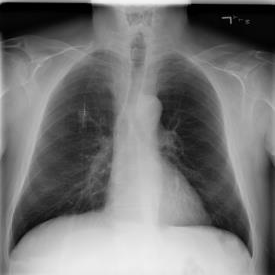

The COVID-19 disease was first discovered in Wuhan, China, and spread quickly worldwide. After the COVID-19 pandemic, many researchers have begun to identify a way to diagnose the COVID-19 using chest X-ray images. The early diagnosis of this disease can significantly impact the treatment process. In this article, we propose a new technique that is faster and more accurate than the other methods reported in the literature. The proposed method uses a combination of DenseNet169 and MobileNet Deep Neural Networks to extract the features of the patient's X-ray images. Using the univariate feature selection algorithm, we refined the features for the most important ones. Then we applied the selected features as input to the LightGBM (Light Gradient Boosting Machine) algorithm for classification. To assess the effectiveness of the proposed method, the ChestX-ray8 dataset, which includes 1125 X-ray images of the patient's chest, was used. The proposed method achieved 98.54% and 91.11% accuracies in the two-class (COVID-19, Healthy) and multi-class (COVID-19, Healthy, Pneumonia) classification problems, respectively. It is worth mentioning that we have used Gradient-weighted Class Activation Mapping (Grad-CAM) for further analysis.

翻译:COVID-19 疾病在中国武汉首次发现,并迅速蔓延到全世界。在COVID-19 流行病后,许多研究人员开始寻找一种方法,利用胸前X光图像诊断COVID-19 。早期诊断该疾病可以大大影响治疗过程。在本篇文章中,我们提出了一种比文献中报告的其他方法更快和更准确的新方法。拟议方法使用DenseNet169 和移动网络深神经网络的组合来提取病人X光图像的特征。在使用单向特征选择算法后,我们改进了最重要的特征。然后,我们将选定特征用作对光GBM(轻度推动机)算法的投入。为评估拟议方法的有效性,使用了ChestX-光8 数据集,其中包括病人胸部的1125 X光图像。拟议方法在两类(COVID-19,健康价值)和多级(COVID-19)中达到了98.54%和91.11%的缩略图。我们分别使用了“高度”的GRAMA-GRA级(C) 分别用于健康等级分析。